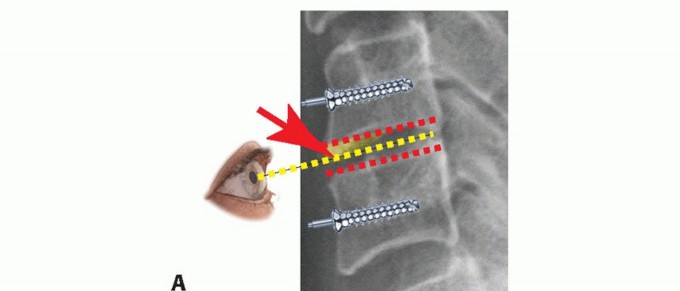

### FIG 3 • MRI and CT scans may provide complementary information in delineating bony versus soft tissue masses. A. On the axial MRI, the compressive lesion has the appearance of a soft disc. B. A CT scan through the same level, however, demonstrates the pathology to be an ossified disc. Similarly, CT scans can help differentiate disc herniations from OPLL. If a high-quality MRI is available but questions remain regarding bony anatomy for the purposes of surgical planning, a noncontrast CT scan provides complementary information (eg, differentiating soft disc versus ossified disc or OPLL) (FIG 3). ## DIFFERENTIAL DIAGNOSIS Cervical radiculopathy Cervical myelopathy Brachial plexus injury Complex regional pain syndrome or reflex sympathetic dystrophy Thoracic outlet syndrome Inflammatory arthropathy Spinal cord tumor Angina Shoulder pathology Peripheral nerve compression (eg, carpal or cubital tunnel syndrome) Diabetic neuropathy Multiple sclerosis Syringomyelia Stroke Guillain-Barré syndrome Normal pressure hydrocephalus Spinal cord tumor ## NONOPERATIVE MANAGEMENT Nonoperative management should be considered as the initial mode of treatment for most patients with radiculopathy. Nonsurgical treatment typically includes physical therapy, traction, pain medication, cervical collars, and epidural injections. It is not clear if nonoperative modalities alter the natural history, but they can provide pain relief while the natural history runs its course. ## SURGICAL MANAGEMENT Surgical intervention is indicated for radiculopathy in patients with persistent symptoms resistant to nonoperative care, progressive weakness, or instability. Common surgical approaches to radiculopathy include ACDF versus posterior laminoforaminotomy.11 ## Preoperative Planning The surgeon should evaluate imaging studies for anatomic variations, such as medial aberrancy of the vertebral artery. To perform a safe but complete and adequate neural decompression, high-quality illumination and magnification are essential. An operating microscope provides illumination and visualization superior to that of loupes and headlights, but either method can be used. Another advantage of the microscope is that the view obtained by the assistant is the same as that of the operating surgeon. If the surgeon chooses to use the microscope, given the smaller field of view, it is imperative to continuously adjust the viewing angle such that a line of sight parallel to the disc space is achieved (FIG 4). If this is not done, the surgeon may inadvertently stray away from the disc space, veer into one vertebral body or the other, and not proceed 3 to the back of the disc space where the decompression needs to occur.

### FIG 4 • Line of sight. When using the microscope, it must be angled properly to provide a parallel view of the disc space to facilitate decompression and endplate preparation. Endplate preparation should proceed in a parallel fashion (dotted red lines) (A) centered on the disc space to achieve a rectangular space for graft insertion. Parallel, wide preparation of the disc space also makes decompression easier to perform and ensures that the decompression is centered on the disc space. B,C. If the line of sight is not maintained, one may err into the vertebral bodies above and below rather than progressing toward the area at the disc level that requires decompression. To achieve parallel surfaces, the inferior endplate of the cephalad vertebra typically requires greater preparation because it is concave. In contrast, the superior endplate of the caudal vertebra is flatter and requires less preparation. C. Proper line of sight is facilitated by removing the anterior lip (arrow, shaded yellow), which allows for better visualization of, and access to, the posterior disc space. ## Positioning The patient is positioned with a bump under the scapula and the occiput on a foam doughnut to prevent pressure necrosis. The amount of extension tolerated preoperatively without excessive pain or neurologic symptoms is recreated. ## Approach A standard Smith-Robinson approach to the anterior cervical spine is used for most cases from C2 to T2. ## TECHNIQUES